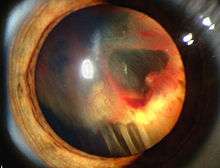

Signs and symptoms associated with VHL disease include headaches, problems with balance and walking, dizziness, weakness of the limbs, vision problems, and high blood pressure. Conditions associated with VHL disease include angiomatosis, hemangioblastomas, pheochromocytoma, renal cell carcinoma, pancreatic cysts (pancreatic serous cystadenoma), endolymphatic sac tumor, and bilateral papillary cystadenomas of the epididymis (men) or broad ligament of the uterus (women).[5][6] Angiomatosis occurs in 37.2% of patients presenting with VHL disease and usually occurs in the retina. As a result, loss of vision is very common. However, other organs can be affected: strokes, heart attacks, and cardiovascular disease are common additional symptoms.[3] Approximately 40% of VHL disease presents with CNS hemangioblastomas and they are present in around 60-80%. Spinal hemangioblastomas are found in 13-59% of VHL disease and are specific because 80% are found in VHL disease.[7][8] Although all of these tumours are common in VHL disease, around half of cases present with only one tumour type.[8]

There is no way to reverse VHL mutations, but early recognition and treatment of specific manifestations of VHL can substantially decrease complications and improve quality of life. For this reason, individuals with VHL disease are usually screened routinely for retinal angiomas, CNS hemangioblastomas, clear-cell renal carcinomas and pheochromocytomas.[16] CNS hemangioblastomas are usually surgically removed if they are symptomatic. Photocoagulation and cryotherapy are usually used for the treatment of symptomatic retinal angiomas, although anti-angiogenic treatments may also be an option. Renal tumours may be removed by a partial nephrectomy or other techniques such as radiofrequency ablation.[7]